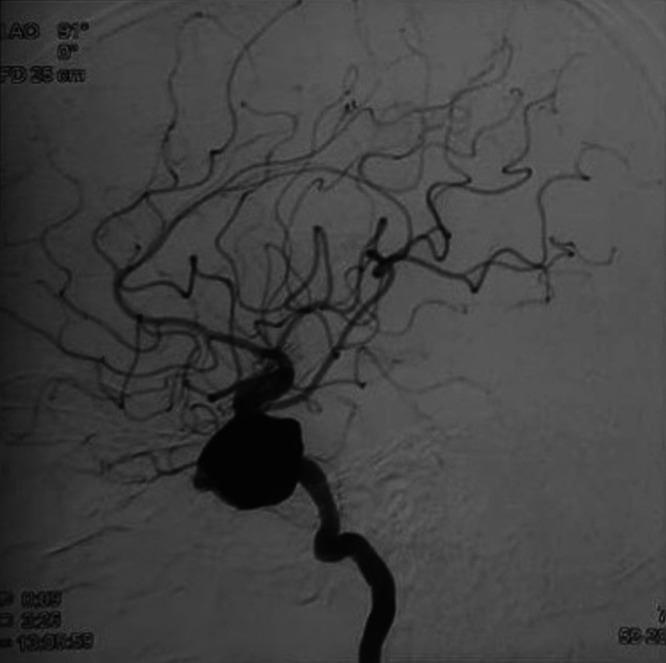

The best treatment option for giant intracranial aneurysms (GIAs) is still debated. The authors report a case of a giant thrombosed cavernous carotid artery (CCA) aneurysm for which two sessions of flow diverter (FD) placement failed, leading to bilateral blindness.

A 66-year-old man presented to an outside center with a history of rapid-onset right-sided retro-orbital pain, visual deterioration, and restricted eye movements associated with headache, vomiting, and diminished sensations on the right side of the face. He was diagnosed with an unruptured thrombosed giant CCA aneurysm and was treated twice with unsuccessful FDs. At follow-up, he developed blindness in both eyes. After 1.5 years, he presented to the authors' institution with headache, vomiting, and epistaxis, for which he underwent high-flow external carotid artery-M2 segment of the middle cerebral artery bypass grafting using the radial artery as a conduit and ligation of the internal carotid artery in the neck without any added neurological deficits.

巨大颅内动脉瘤(GIA)的最佳治疗方案仍存在争议。作者报告了一例巨大血栓形成的海绵窦段颈内动脉(CCA)动脉瘤病例,该病例进行了两次血流导向装置(FD)置入均失败,导致双侧失明。

一名66岁男性因快速发作的右侧眶后疼痛、视力恶化、眼球运动受限伴头痛、呕吐及右侧面部感觉减退的病史就诊于外院。他被诊断为未破裂的血栓形成的巨大CCA动脉瘤,并接受了两次FD治疗,但均未成功。随访时,他出现了双眼失明。1.5年后,他因头痛、呕吐和鼻出血就诊于作者所在机构,为此他接受了以桡动脉为血管桥的高流量颈外动脉-大脑中动脉M2段搭桥术,并结扎了颈部的颈内动脉,术后未出现任何新增神经功能缺损。